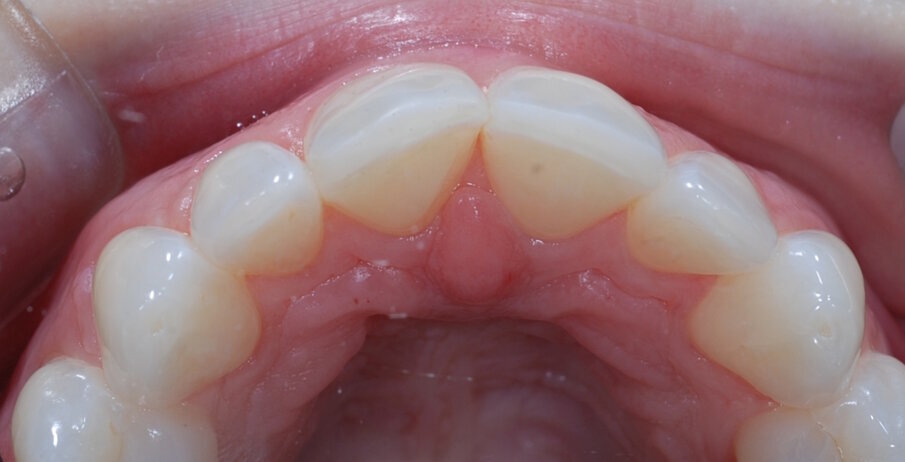

Fig. 6: Pre treatment upper occlusal

She made it clear she was not motivated for fixed orthodontics and was interested to know if her upper anterior teeth could be aligned with the ClearSmile Inman Aligner. After an orthodontic assessment, UR2 was identified as the landmark tooth, and the SpacewizeTM crowding calculator showed that the difference between the available space and required space was 2.2mm.

When the case was submitted to the IAS Academy’s online support along with clinical photographs and SpacewizeTM analysis, the trainers confirmed that it was a suitable case for the ClearSmile Inman Aligner with a combined expander, and would help to unlock the overlapping central incisors. The trainer also said that it may not be possible to completely align the upper arch while the lower arch remained crowded, so a digital setup was requested from the laboratory to ascertain exactly what could be achieved.